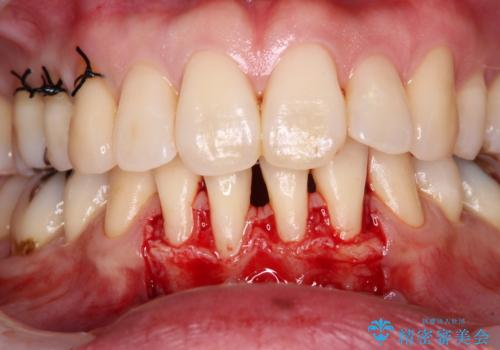

- 矯正治療により下の前歯の歯肉が退縮してしまい、根が見えていることが気になるとのことで来院された患者様です。

歯肉退縮に対して、上顎からの結合組織移植術(CTG)により、歯根の被覆を行うとともに、歯肉の厚みを増すことで将来の退縮リスクを抑制することとしました。